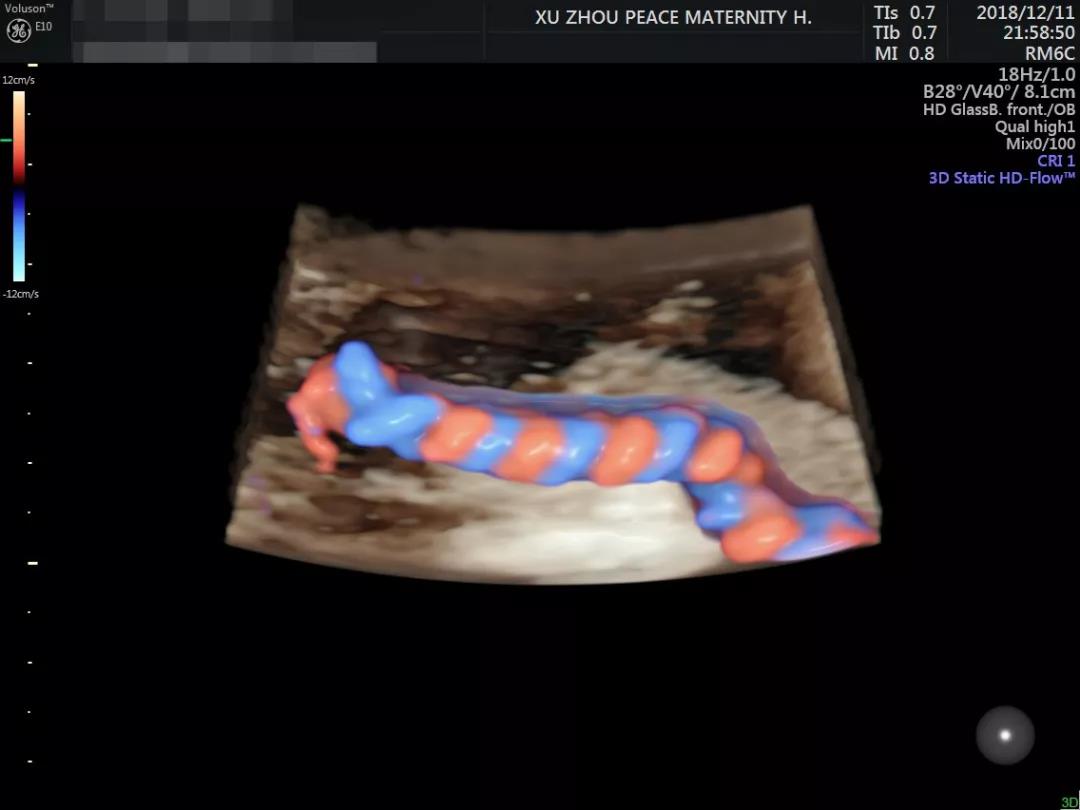

娴熟运用美国E10彩超设备

超高清的四维成像▼